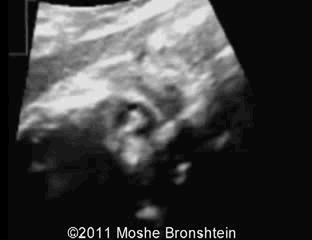

病例 2. 患者 22 岁,G1P0,无明显个人病史和家族病史,其孕 22 周首次超声检查未见异常。孕 34 周时因怀疑巨细胞病毒感染合并严重宫内发育迟缓以及羊水过少和脑室轻度扩张和双侧白内障来我处就诊。

图 3 为以往某孕 15 周的先天性白内障;图 4 为本例孕妇 34 周先天性白内障及永存玻璃体动脉